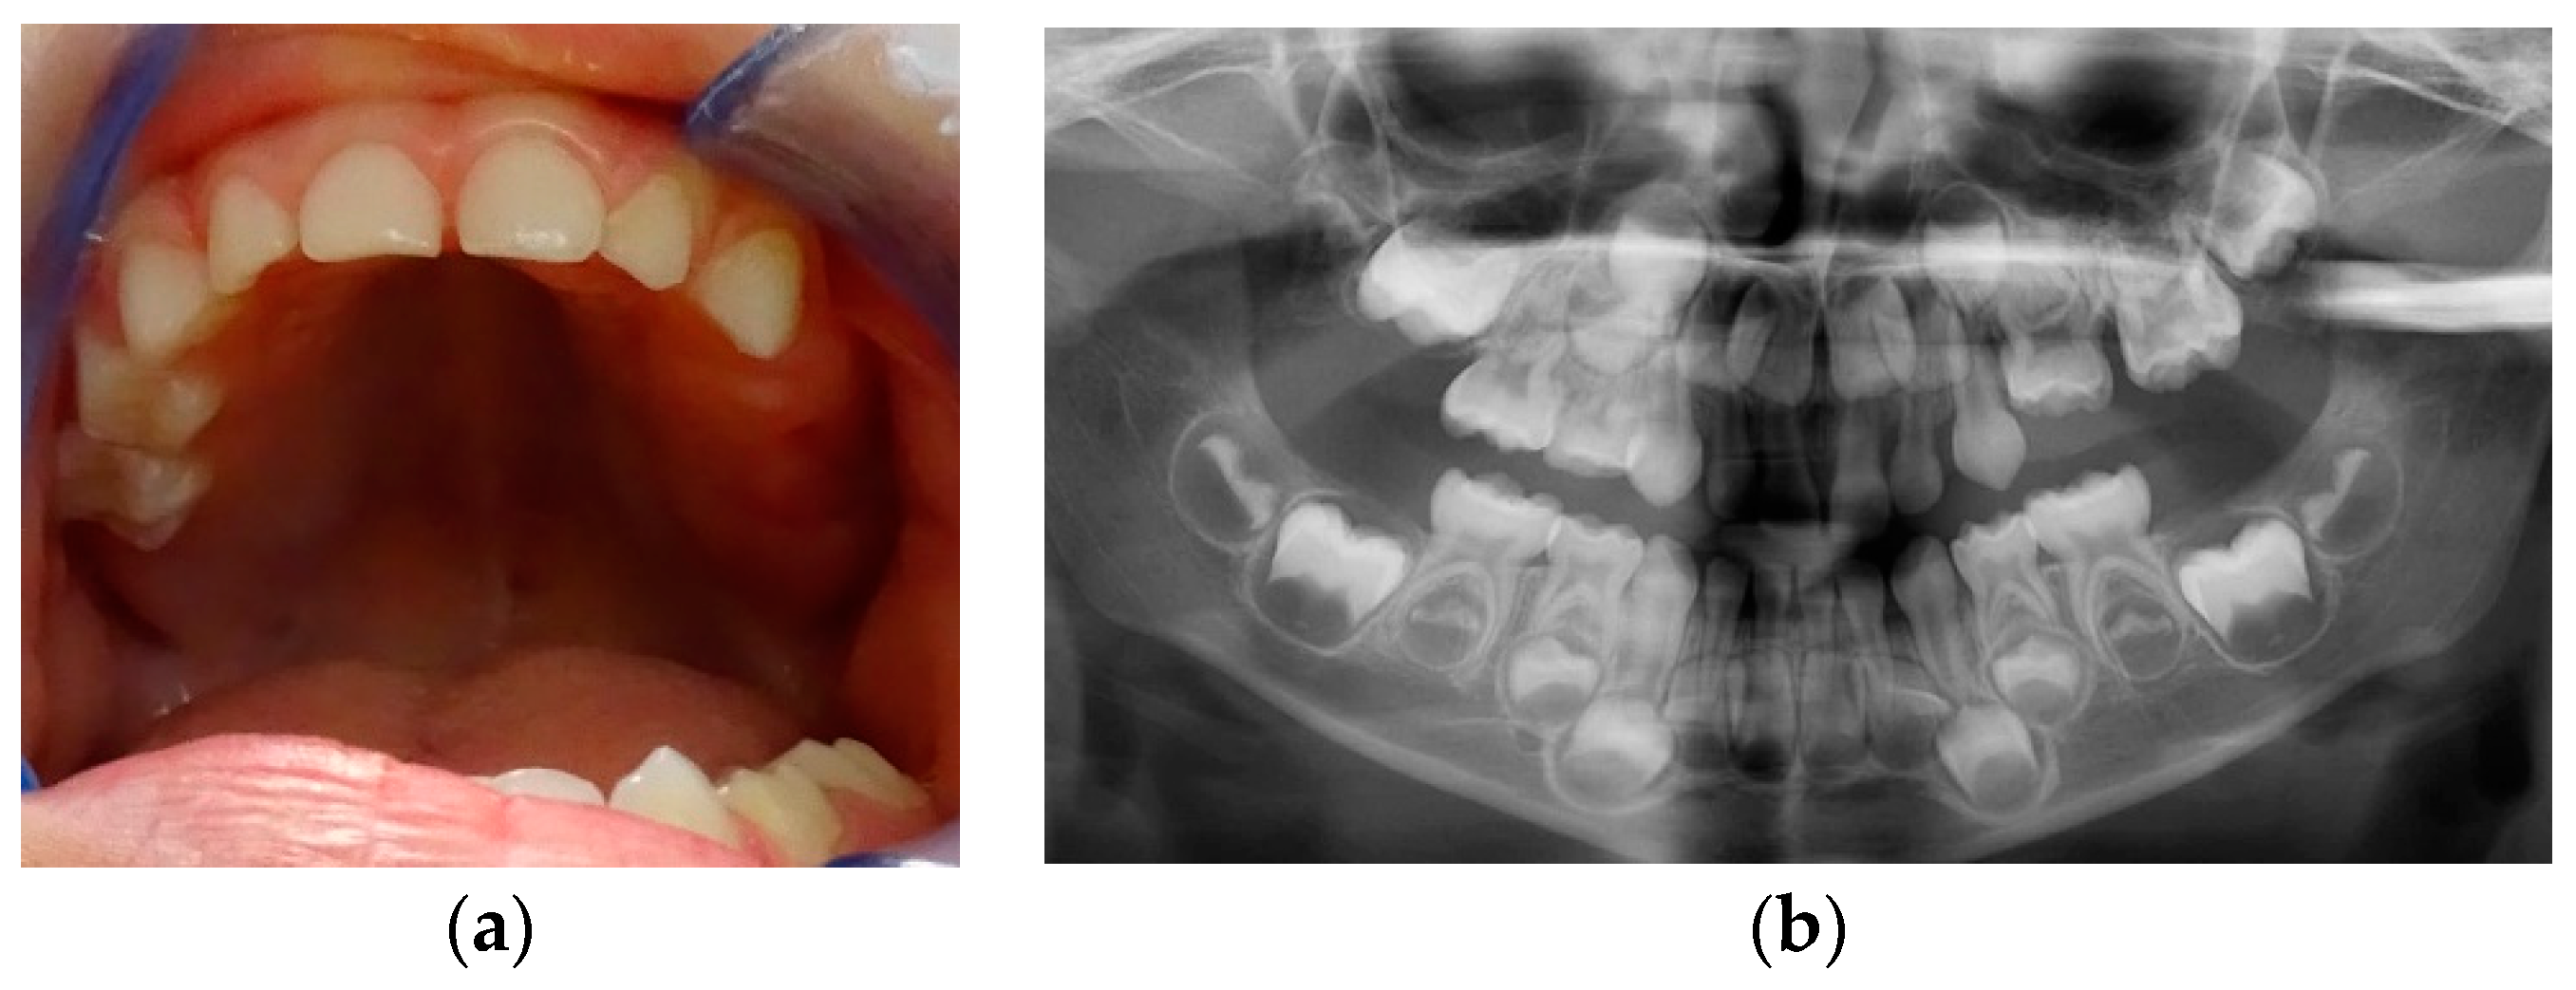

At age 9y 7m, 26 was still not on the arch (Figure 4a). A CT examination was performed. Agenesis of 24, 25 became certain (Figure 4b) and no areas of ankyloses in teeth with eruption failure were found. Decision was taken to remove 63 in order to favour eruption of mechanically impacted 64, but extraction was postponed at family’s request.

Figure 4. Age 9y 7m: a) Clinical aspect; b) CT view.